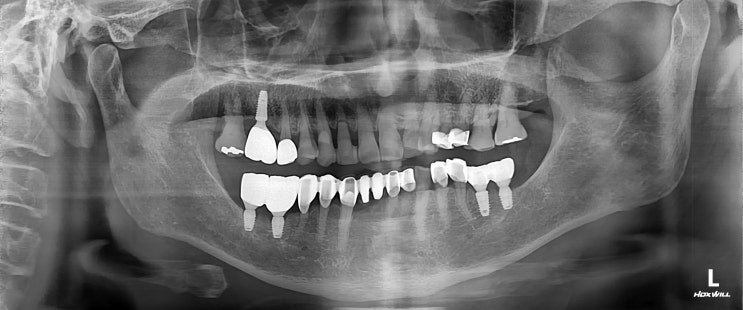

[수서역 치과 전문의] 치아 뿌리 파절로 인한 발치

안녕하세요 수서역 치과 치과 전문의 수서서울삼성치과 원장 이재현입니다 다들 1주간 지속된 비에 큰 피해...

[일원동 치과] 전치부 파절로 인한 임플란트 보철

안녕하세요 수서역 치과 일원동 치과 수서신혼희망타운 치과 수서서울삼성치과 원장 이재현입니다 오늘은 ...